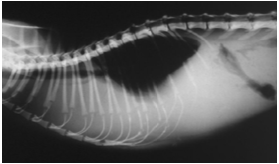

Pneumothorax